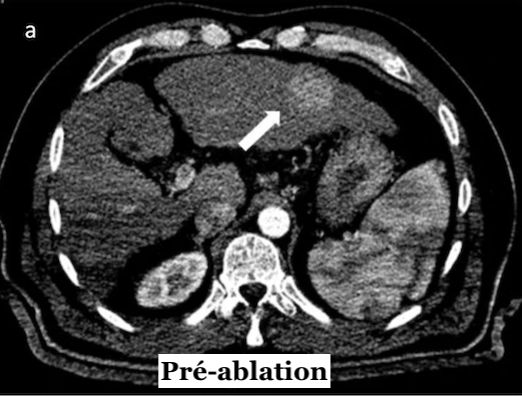

Ils utilisent pour cela la fusion d'images tomodensitométriques intraprocédurales injectées par produit de contraste, pré et post-ablation, ainsi que pour prédire la récidive locale. Ils se proposent également de déterminer un MAM avec lequel une ARF peut être considérée comme réussie et peut donc être utilisée comme un outil intraprocédural pour évaluer le succès du traitement. Les chercheurs ont réuni un total de 110 patients (20 femmes, 90 hommes) présentant 176 carcinomes hépatocellulaires de manière rétrospective. La MAM a été déterminée par fusion d'images intraprocédurales pré et post-ablation en utilisant un logiciel d'enregistrement d'imagerie rigide disponible dans le commerce. La récidive a été évaluée par tomodensitométrie ou IRM injectées à intervalles de 3 à 6 mois.

À l’issue de leurs travaux, les chercheurs ont objectivé que la MAM était le seul prédicteur indépendant significatif de récidive. Pour chaque augmentation millimétrique de la MAM, une réduction de 30% du risque relatif a été identifiée. Aucune récidive n'a par ailleurs été détectée dans les lésions présentant une MAM supérieure à 5mm. Le taux global de récidive a atteint 8,2% (9 sur 110) au niveau du patient et 5,7% (10 sur 173) au niveau de la lésion, avec une MAM médiane de 3,4mm. La période de suivi globale moyenne était de 26,0 ± 10,3 mois.

Ils en ont donc conclu que l’évaluation immédiate de la marge ablative minimale (MAM) peut être utilisée comme un outil intraprocédural de l’ablation de CHC par radiofréquence pour évaluer le succès de ce traitement, avec une MAM supérieure à 5mm considérer une ablation comme réussie.